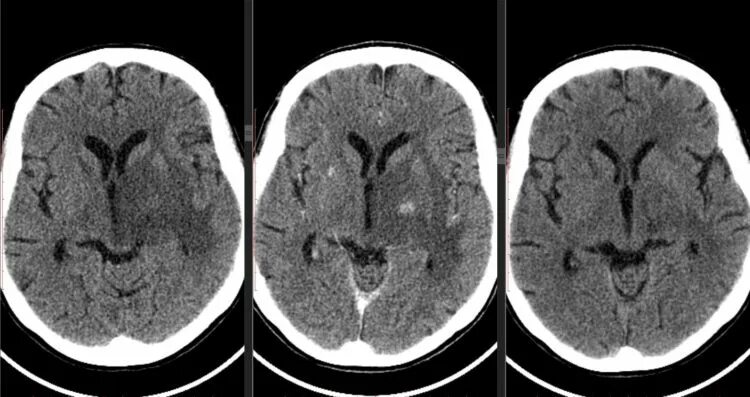

Менингиомы головного мозга мкб